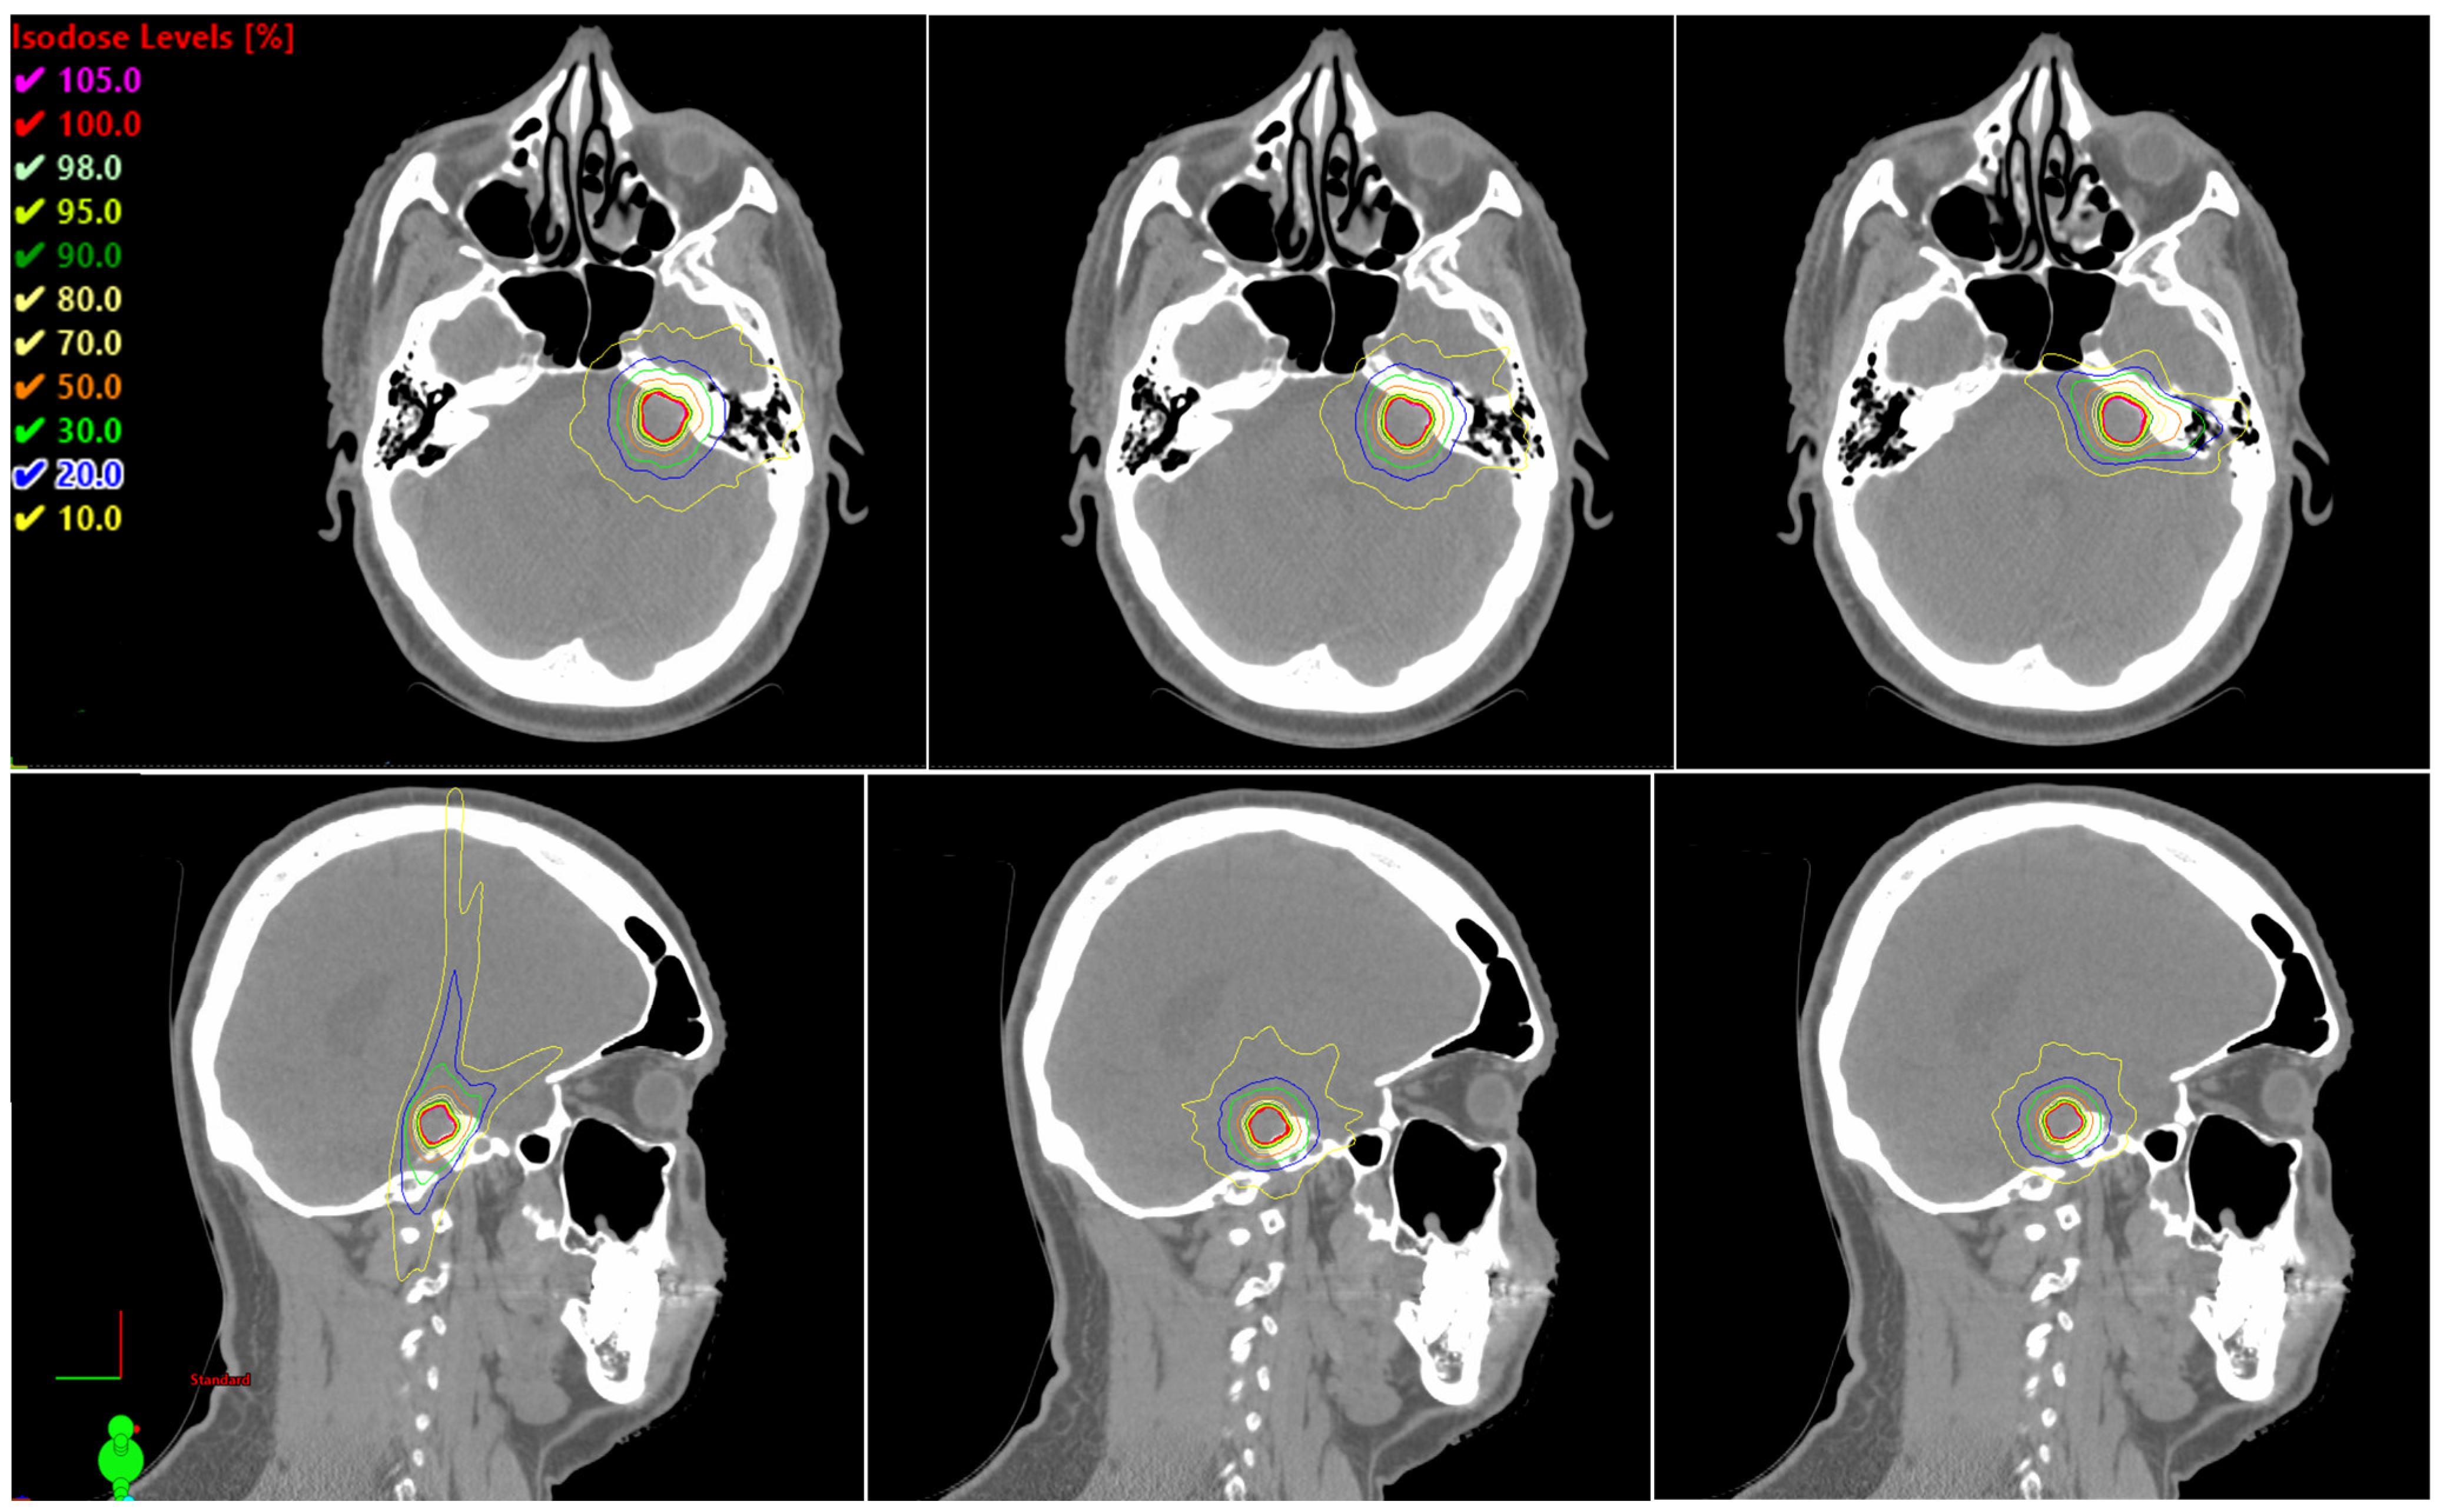

Dosimetric Comparison of Automated Noncoplanar VMAT (HyperArc) Versus CyberKnife for Single-Fraction Vestibular Schwannoma Stereotactic Radiosurgery

Xiong, Z.; Zhang, Y.; Zhou, L.; Xu, K.; Zhang, X.; Bell, L.; Warburton, F.; Huang, D.; Motwani, S.B.; Cathcart, C.S.; et al. Dosimetric Comparison of Automated Noncoplanar VMAT (HyperArc) Versus CyberKnife for Single-Fraction Vestibular Schwannoma Stereotactic Radiosurgery. Cancers 2026, 18, 1207. https://doi.org/10.3390/cancers18081207